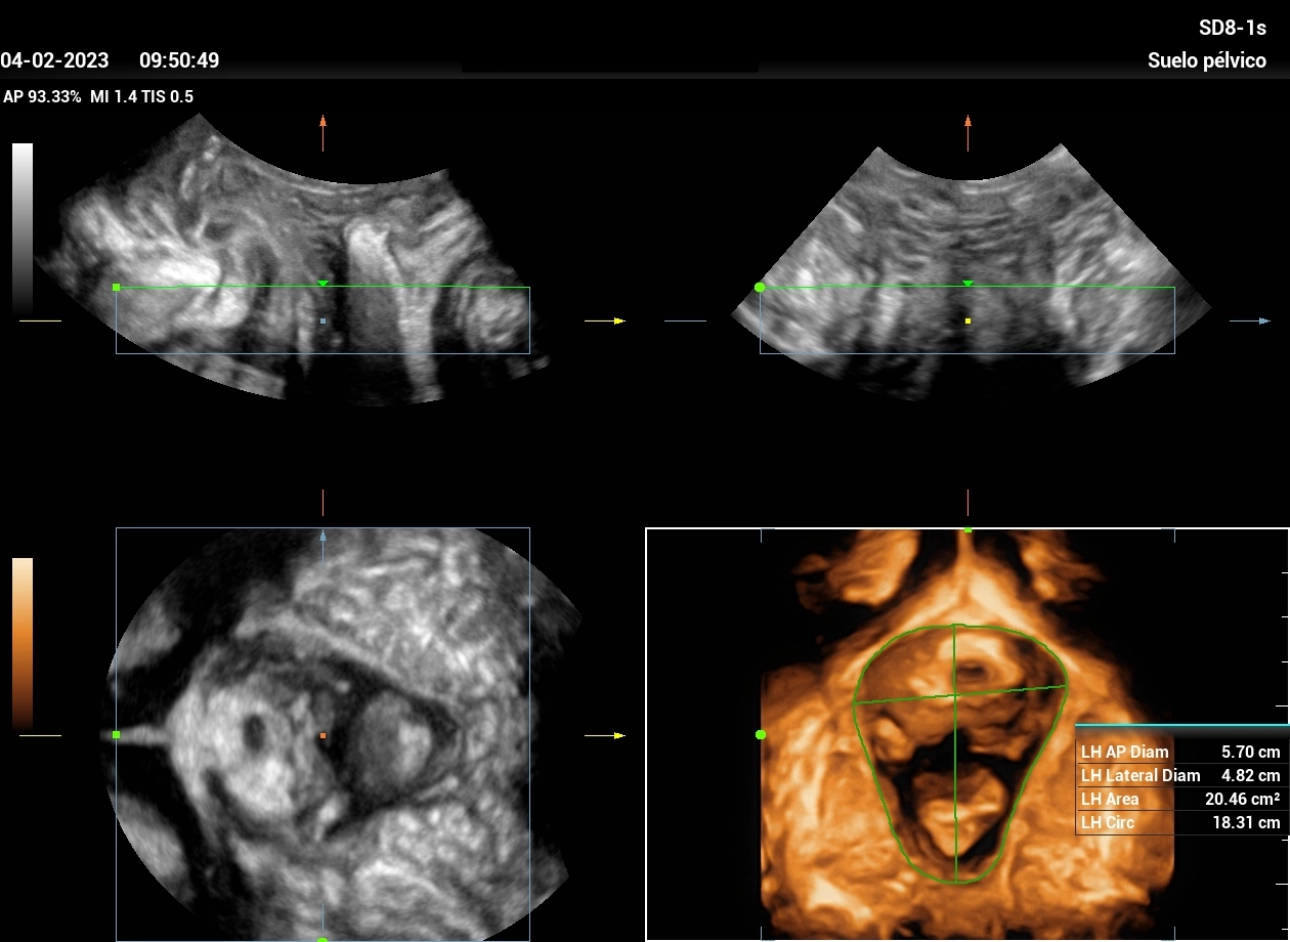

It is examined with color Doppler without filling of the urethra, which infers internal sphincter competence (Figure 3). After evacuating the bladder, a post-micturition residue of 8 ml and a detrusor thickness of 3.4 mm were found. When evaluating the hiatus in 3D, at rest and after Valsalva, a ‘normal’ distensibility of the levator hiatus is observed. (Figures 4 and 5)

stress-urine-fig4

Figure 4: allows evaluation of the hiatus area in the coronal plane, with the automatic measurement software of the equipment.

stress-urine-fig5

Figure 5: Measurement of Levator Hiatus area in Valsalva maneuver, where we can appreciate a ‘normal’ distensibility of the levator hiatus is observed (20.46cm2); which does not generate symptoms in the patient.